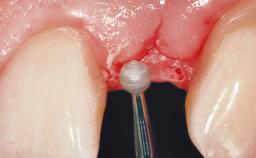

After the placement of three diameter-reduced two-piece implants the bone is augmented with autologous bone chips and DBBM particles to enlarge the crest volume. The surgery is completed with the application of two membrane layers and primary wound closure.

Bone Augmentation Horizontal|Simultaneous

Augmentation Materials Autogenous chips|Xenogenous|Membrane

Bone Volume Deficient horizontally, allowing simultaneous augumentation